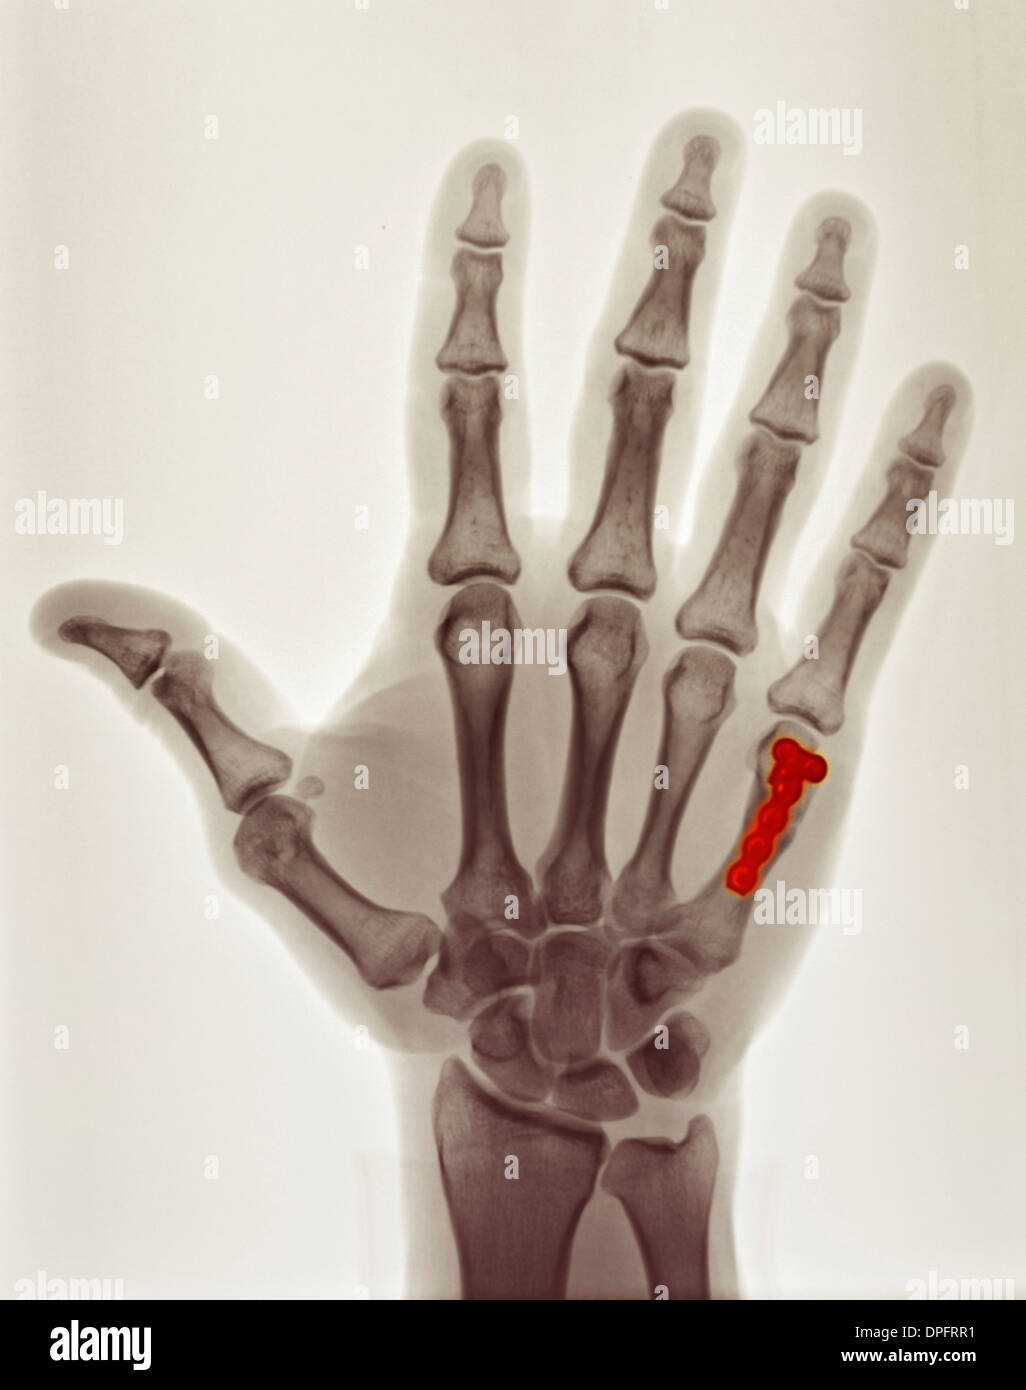

Boxer fracture. Radiograph shows a fracture of the fifth metacarpal X Ray Boxer's Fracture a boxer’s fracture is a fracture of the 5th metacarpal neck, named for the classic injury mechanism involving direct trauma to a clenched fist. Pain or swelling along the 4th or. Lateral views can help with assessing angulation and other. Ap and oblique view should be obtained; Treatment varies depending on whether. a boxer's fracture, or metacarpal fracture,. X Ray Boxer's Fracture.